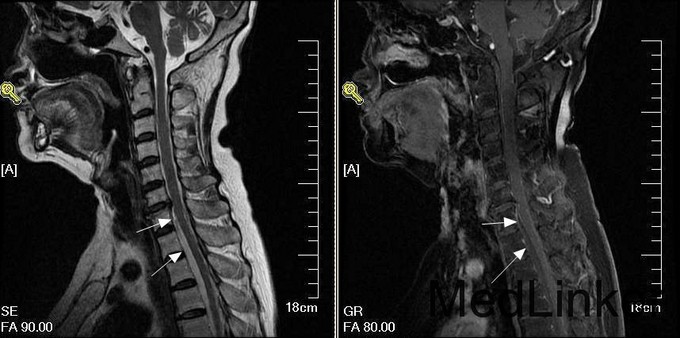

神经内科查体:神清、语明,面纹对称,伸舌居中,双上肢活动既感觉基本正常,平脐水平以下深浅感觉障碍,双下肢肌力0级,腱反射未引出,双侧巴氏征-,颈强+。患者存在感觉平面、截瘫及尿边障碍,根据患者临床表现考虑存在脊髓病变,遂急诊行颈段MRI检查,见图:

诊断:脊髓硬膜外出血 建议患者手术治疗,但患者家属要求转院治疗。